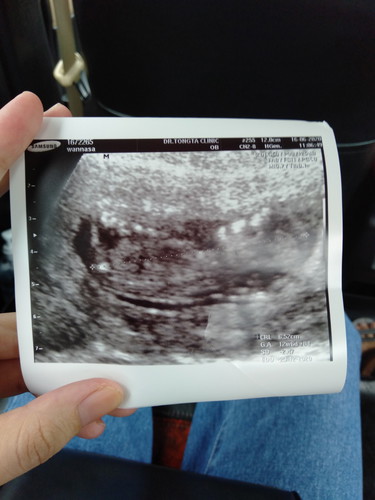

แบบนี้เห็นเพศรึยัง 12w6d

แม่ๆคะแบบนี้เห็นรึยังคะเราไปซาวมาคุณหมอยังไม่ได้บอกว่าเพศอะไรอยากทราบว่าจะรู้เพศน้องได้กี่สัปดาห์คะ ขอบคุณค่ะ

ช่วง 20w จะชัดค่ะ ต้องดูระหว่างขานะคะ ถึงจะเห็น อันนี้น้องหันข้าง เพศยังมองไม่ชัดด้วยค่ะ

20wค่ะ ตอนนี้น้องยังตัวเล็กอยู่